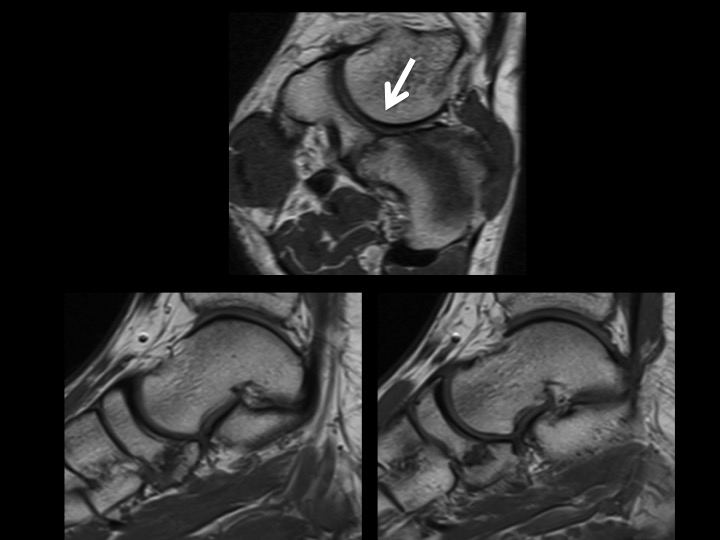

30M chronic, worsening heel pain

Although there have only been 9 cases of navicular-cuboid coalition reported up to 2012 (up to and including the reference for case #1390), here is another case in a 30M with bilateral non-osseous navicular-cuboid coalition (white arrows; changes more pronounced on the left). He has left-sided Haglunds deformity, which relates to his symptoms. Although the 4 cases reported in the reference from #1390 had midfoot pain, I am struck that this patient, and the 10 yr old from #1390 both present with hindfoot pain. I imagine the midfoot tarsal coalition might have a global impact on foot biomechanics.

navicular-cuboid coalition